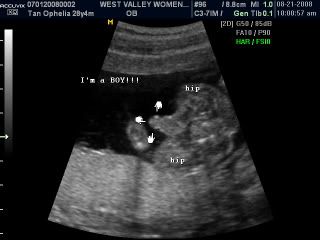

On Thurday... We went for a detailed scan. Mummy beanie told the sonographer that during week 12, when we were there, she told us that baby beanie is a boy and so... she check it once again. And she said, "Well... its still there, he is still a boy!" Haha... and we laughed. The scan went on really well. Baby beanie's very healthy and he is growing really well! Here's mummy beanie at the sonographer's diagnostic room and some pictures of baby beanie at 19 weeks! Enjoy!

His pee pee!

His information! Only weighs a mere 312g... So cute! The sonographer says he is about... 8 inches! Awwww...